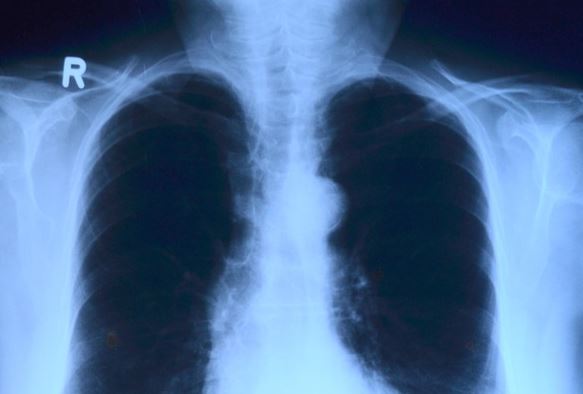

Basándose en esto, los científicos estadounidenses desarrollaron un algoritmo capaz de detectar nódulos pulmonares malignos, a veces minúsculos, a partir de resultados de un TAC -tomografía axial computarizada- del tórax, con un empeño y precisión igual o mejor que el de los radiólogos.

Para ello, “entrenaron” al sistema en 42.290 imágenes de tomografía computarizada y encontraron que el sistema de inteligencia artificial fue capaz de detectar los módulos con una precisión del 94% en 6.716 casos de prueba.

Mozziyar Etemadi, profesor de Medicina y de Ingeniería en Northwestern y uno de los autores de este artículo, explica que los radiólogos generalmente examinan cientos de imágenes bidimensionales en una sola tomografía computarizada, pero este nuevo sistema permite analizar instantáneas en 3D.

“La inteligencia artificial en 3D puede ser mucho más sensible en su capacidad de detectar el cáncer de pulmón temprano que el ojo humano que mira imágenes en dos dimensiones”, resume este investigador.